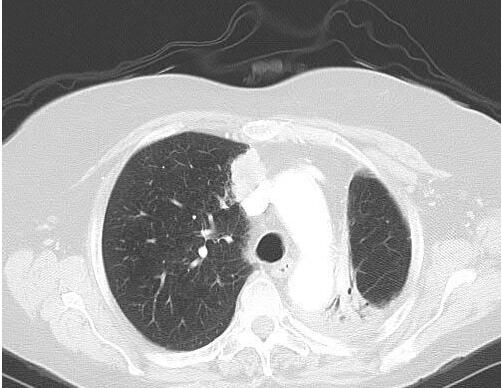

6年后,CT显示右上叶内侧有新发增强肿块,怀疑转移或新原发性肺癌(图2)。脑扫描显示转移疾病阴性。PET显示在预期区域有摄取和右肺门淋巴结有不确定的摄取(图3),但为阴性。 肺功能检查

图2